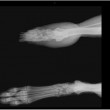

Rocky doveva essere operato con urgenza: non c’era altro da fare che amputare la zampa. L’operazione però costava 2.500 dollari e così è scattata la gara di solidarietà sul web: i fondi necessari sono stati raccolti, Rocky è stato operato e ora sta bene.

Sulla pagina Facebook dell’organizzazione sono state postate le foto di Rocky prima e dopo l’amputazione: “Considerando tutto quello che ha passato, penso che se la caverà alla grande”, ha raccontato la veterinaria Maria Bromme.